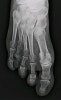

X-ray : 선천성 단중족증(Congenital brachymetatarsia)

실제로는 발가락이 짧은 것이 아니고 중족골이 짧은 것으로 가장 많은 것은 제4중족골 단축증입니다.

그 외에 엄지발가락 등 다양하게 짧기도 하고, 좌우 모두에 생긴 경우도 있습니다.